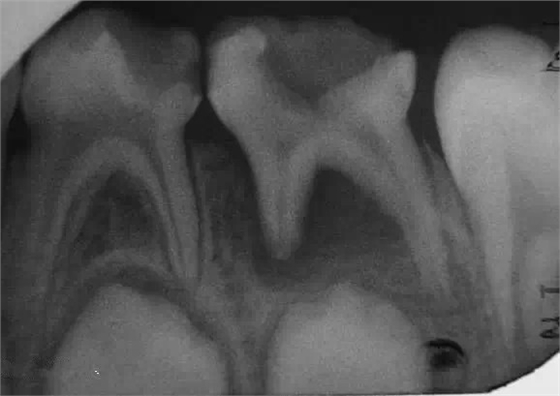

這是我當(dāng)年老師叫我記住的一個數(shù)字。這個是乳牙A--E牙根開始吸收的時間,很順口,用于判斷乳牙牙根吸收的時間,結(jié)合乳恒牙正常替換時間和次序,正確選擇對乳牙的治療時機(jī)和手段。舉例子,下頜乳牙D牙根開始吸收的時間是7周歲,今年患者為10周歲半,牙根吸收得差不多了!

乳牙急性根尖周炎的應(yīng)急處理,首先應(yīng)建立髓腔引流,用快速鋒利的渦輪機(jī)牙鉆開髓,開放髓腔,使炎性滲出物或膿液通過根管引流。 (福建醫(yī)大口腔醫(yī)院 高生輝老師的圖片)

(以上圖片引用自福建醫(yī)大附屬口腔醫(yī)院兒童科 高生輝老師的課件,非常感謝!)

總結(jié)一下,1,在決定牙髓治療前一定要拍個X光片。有助于后續(xù)治療。